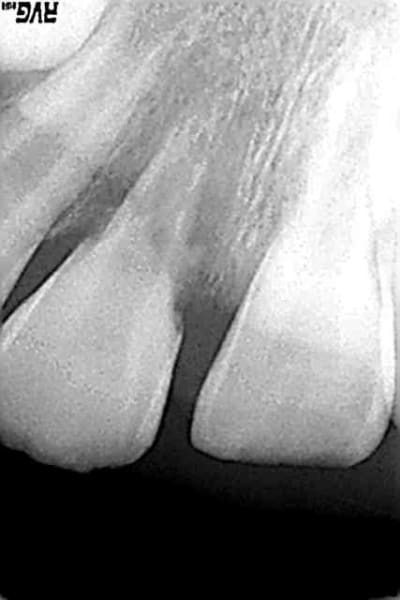

patient 8 ans vu aujourd'hui

chute le 29/08/2006(clermond ferrand)

impaction 21 et 22(21 fracturée au 1/3 coronaire)

luxation totale de 11

réimplantation au bout de 4 h(conservée ds ..rien:compresses sèches mais pas traitée...)

mise en place d'un arc de contention(Duclaux)

contention enlevée il y a 15 jours(dc 4 semaines de contention)

que feriez vous avec 11,sachant qu'il y a ankylose et aucune mobilité mais aussi rhyzalyse importante?